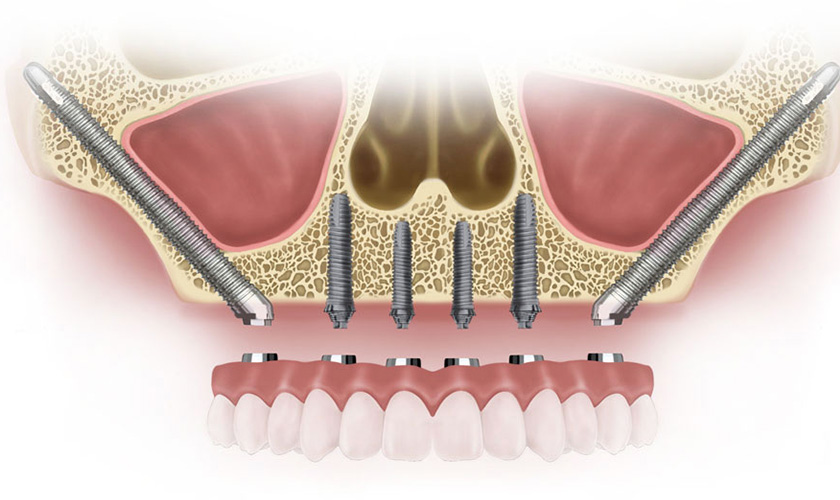

Thay vì cắm thẳng vào xương hàm thì kỹ thuật cấy Implant xương gò má sẽ được đặt vào xương gò má bằng một loại trụ Implant đặc biệt. Trụ có hình dáng thon dài và gấp khúc theo góc độ của từng vị trí răng mất. Tùy thuộc vào tình trạng của khách hàng có thể cấy ghép 2 hoặc 4 trụ để hỗ trợ cầu răng bán phần hoặc toàn phần.

Implant xương gò má là kỹ thuật phục hình răng chuyên sâu được Giáo sư Branemark giới thiệu vào năm 1998. Đây là giải pháp “cứu cánh” cho những trường hợp đặc biệt như khách hàng bị tiêu xương hàm trên trầm trọng, thất bại sau ghép xoang cấy implant thông thường, bị cắt bỏ xương hàm sau điều trị ung thư hay dị tật hàm mặt.

Ngoài những ưu điểm tương tự như kỹ thuật trồng răng Implant thông thường, cấy ghép xương gò má còn một lợi ích nổi trội chính là không cần tiến hành ghép xương. Điều này cực kỳ có ý nghĩa với những khách hàng có mật độ xương hàm mỏng hay bị tiêu xương quá nhiều. Với những trường hợp đã từng bị đào thải Implant hoặc không thể cấy Implant thì đây cũng là một giải pháp hữu hiệu.

Phương pháp cấy Implant xương gò má cũng có thể làm giảm số lượng implant nâng đỡ vùng răng trước do neo chặn implant ổn định đạt được trong xương gò má, do đó, giảm các biến chứng có thể xảy ra.